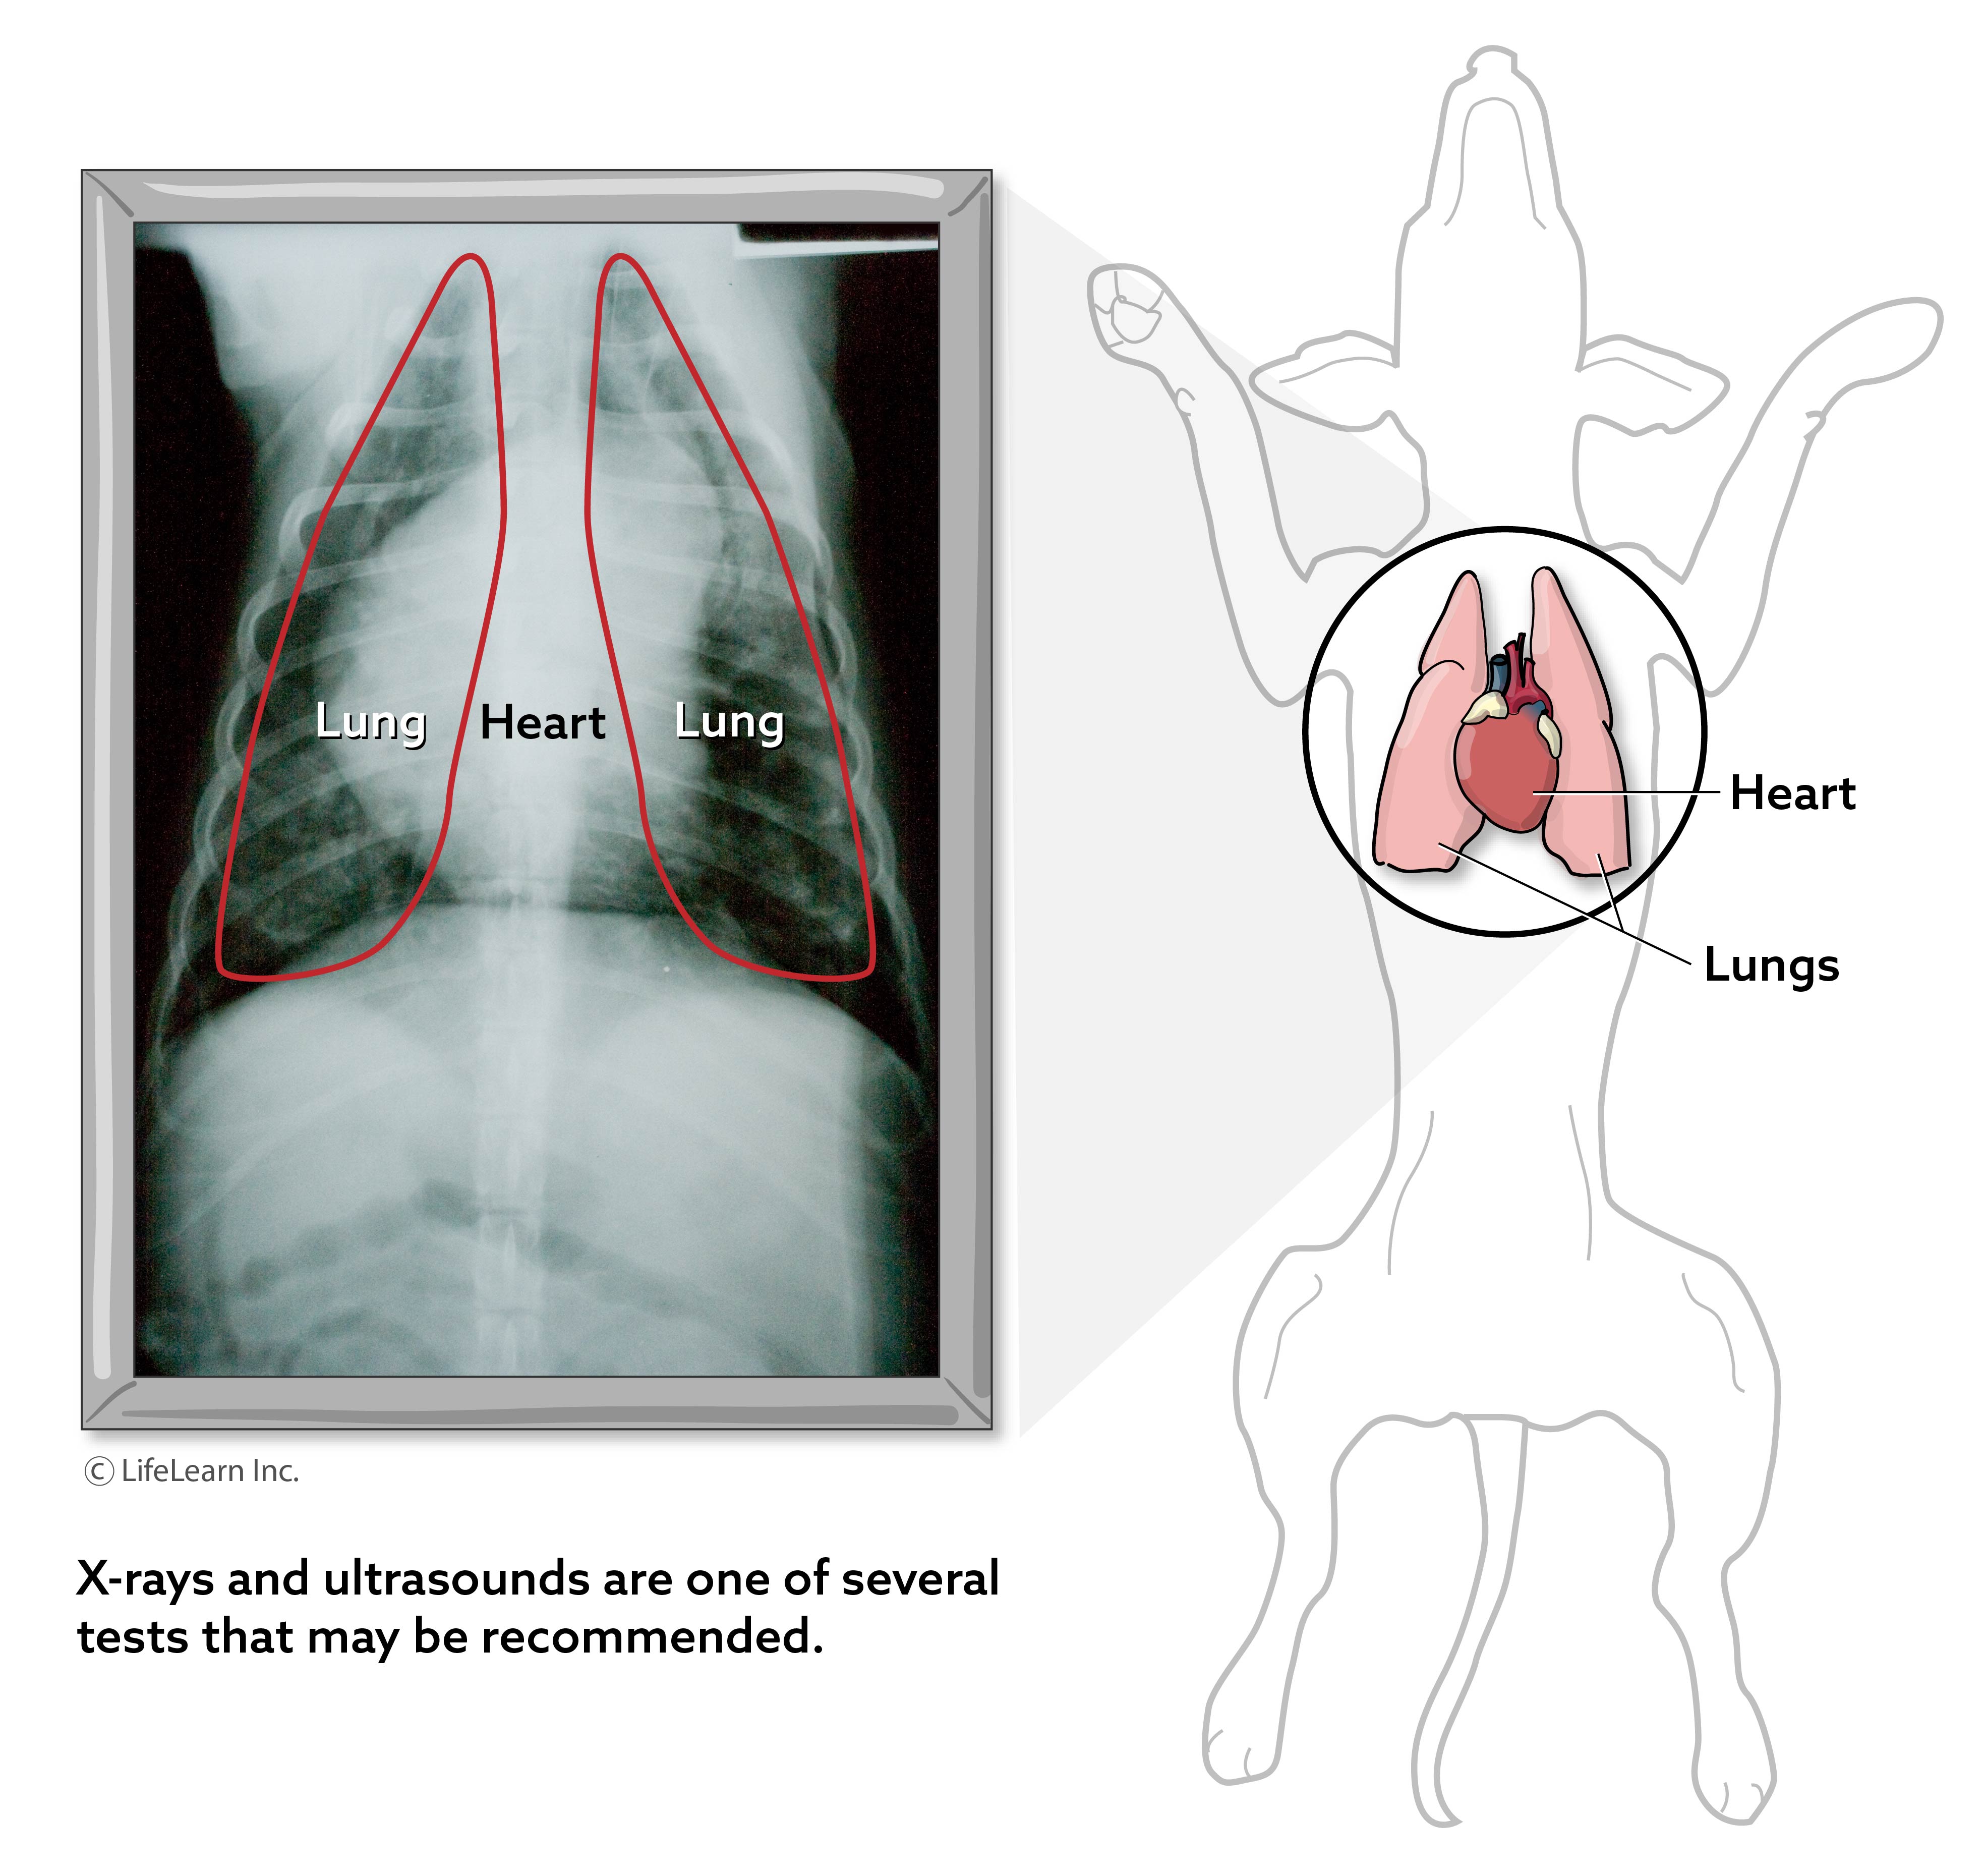

Chest X-Rays (Three-View Thoracic X-Ray)

Required before tumor removal surgeries to rule out metastasis (spread of cancer).

Evaluates heart and lung health for pets undergoing major procedures.

"pet X-ray for surgery clearance"

CT scans or ultrasounds may be recommended for complex cases.

Helps evaluate internal tumors, fractures, or internal organ abnormalities.